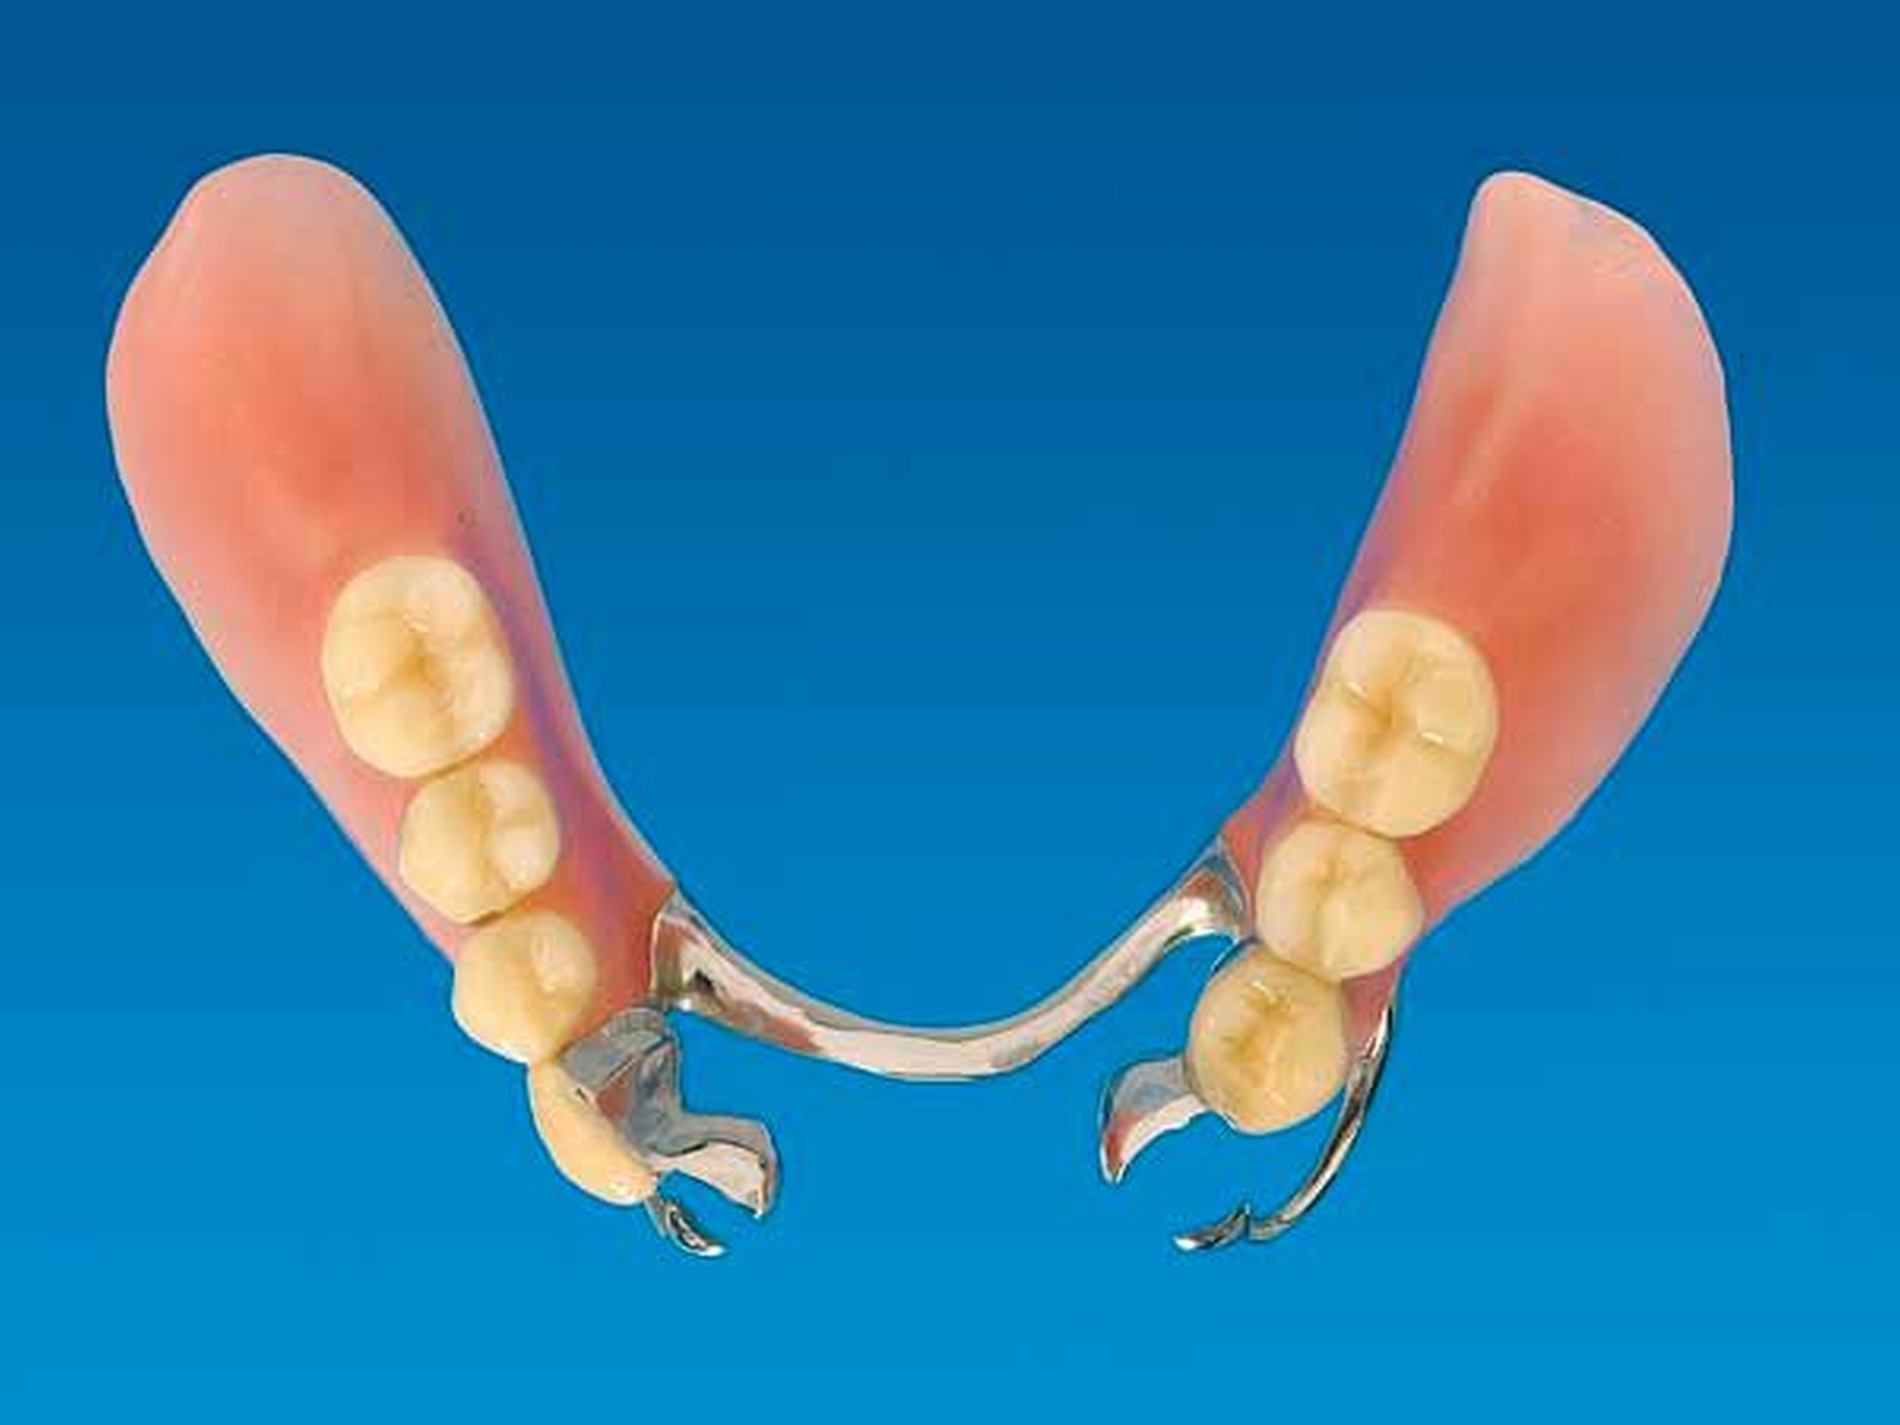

Die Patientin konnte mit einer Modellgussprothese und zwei RPI-Klammern an den Zähnen 34 und 45 erfolgreich versorgt werden (Abbildungen 3 und 4). RPI steht für Rest (meist sattelferne Abstützung), Proximal Plate (approximale Führungsfläche), l-bar (i-förmiger Retentionsteil). Das RPI-Klammersystem wurde 1963 von Kratochvil [Kratochvil, 1963] eingeführt und von Krol 1973 [Krol, 1973] weiterentwickelt. Das Klammersystem ist kein Exot. Es findet sich in nahezu allen internationalen Standardlehrbüchern der Prothetik und gilt als das mit am besten bewährte Klammersystem für die bilaterale Freiendsituation [Davenport et al., 1992; Krol, 1999; Carr et al., 2000].

Die proximale Platte der RPI-Klammer blockiert wirkungsvoll dislozierende Sattelbewegungen (Abbildung 5), der von gingival inserierende Retentionsarm ist nahezu unsichtbar. Aufgrund des langen Federweges ist der Retentionsarm praktisch ermüdungsfrei und lässt sich gegebenenfalls leicht aktivieren. Die Abstützung liegt sattelfern analog einer Back-Action-Klammer. Für die RPI-Klammer wird am Ankerzahn neben der üblichen mesialen Klammerauflage die disto-approximale Wand parallel zur Einschubrichtung im Schmelz präpariert (Abbildung 6). Die Präparation sollte mindestens 1 mm oberhalb der Papille enden. Die präparierte Fläche dient der flächigen Anlage der proximalen Platte (Abbildung 3).